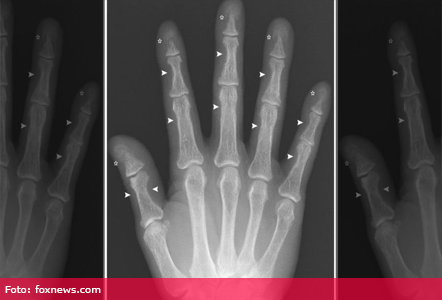

Astfel, niveluri ridicat al hormonilor paratiroidieni a accelerat distrugerea oaselor, iar în consecință s-au micșorat oasele degetelor. Când medicii i-au scos tumoarea, nivelul hormonilor bărbatului s-au normalizat, iar oasele au început să-și revină, potrivit unui raport publicat pe 21 mai in New England Journal of Medicine.

Radiografia mâinii era făcută în mod obișnuit la pacienții suspectați că ar avea glandele paratiroide hiperactive, numit și hiperparatiroidism. Dar astăzi, medicii stabilesc diagnosticul după testele de sânge. Aceste teste s-au îmbunătățit în ultimii 30 de ani și au eliminat necesitatea radiografiei, susține Clarke.

Cazul ilustrează modul în care oasele din corp trec printr-o remodelare constantă. Un set de celule descompun osul și eliberează calciu în sânge, care se numește resorbția osoasă. În cele mai multe dintre aceste cazuri lucrurile revin la normal atunci când glandele hiperactive sunt eliminate, spun experții citați de Fox News.